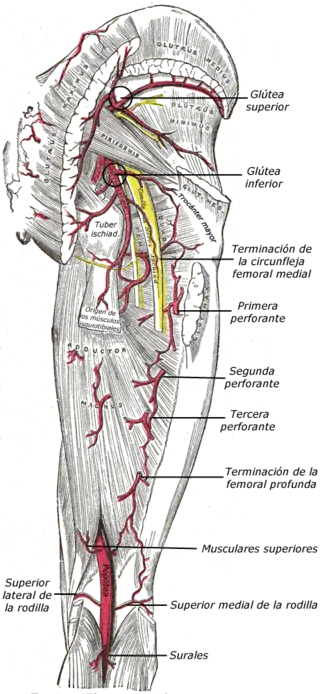

Arterias de las regiones glútea y femoral posterior.